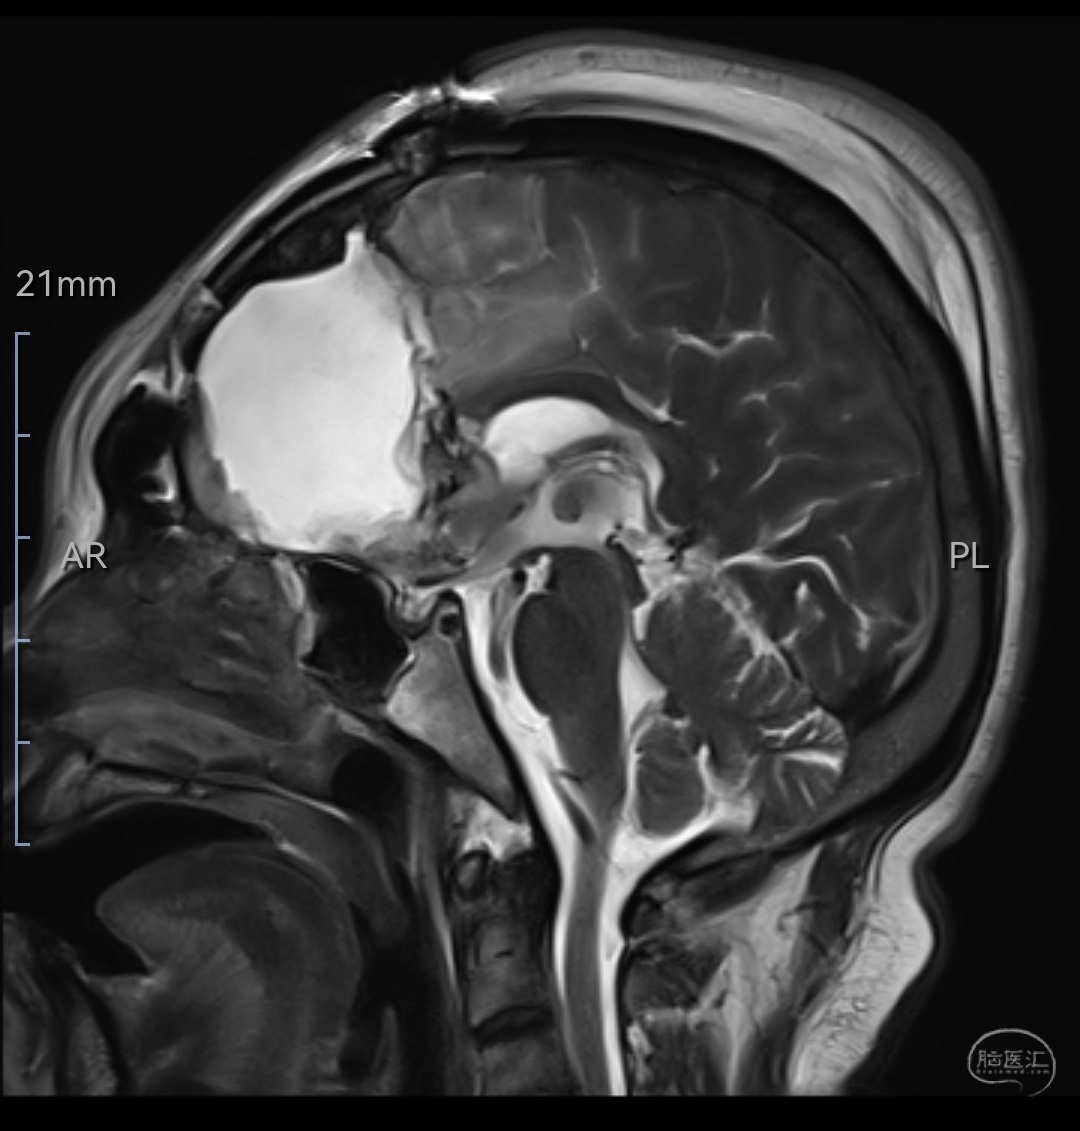

MRIT2相轴位示肿瘤等高信号,位于双侧额叶,左侧为主,已侵犯至胼胝体嘴、膝部及左侧颞岛叶,伴有明显水肿

MRIT2相矢状位示肿瘤位于双侧额叶,左侧为主,已侵犯至胼胝体嘴、膝部